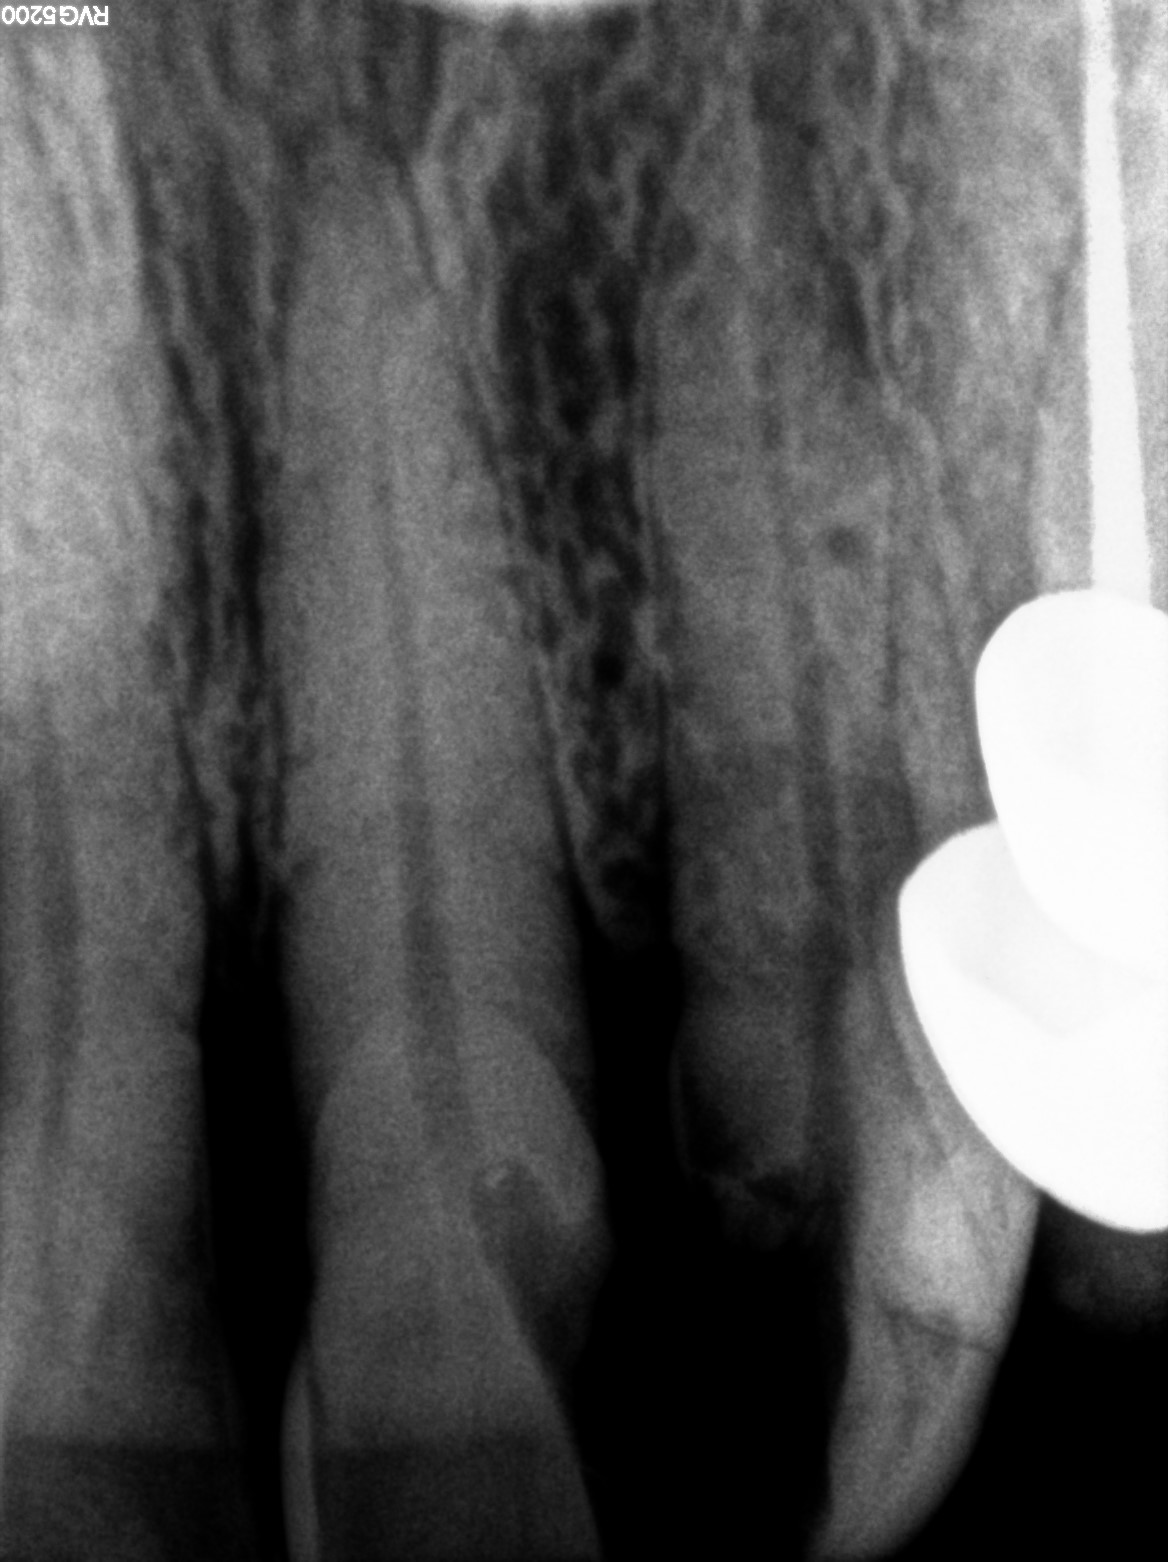

Dental Radiographs FHIR: DocumentReference · LOINC 24641-7

d (12).jpg

24641-7